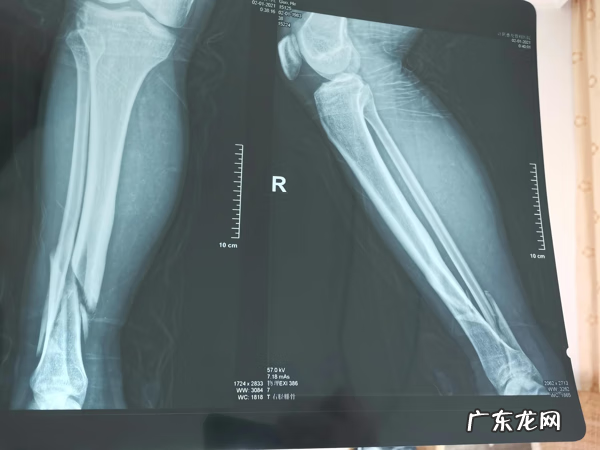

元旦那天晚上骑电瓶车摔跤,导致胫腓骨骨折,1月2日白天做的手术 。手术很成功 。到现在已经20天了,想问有没有相同经历的病友,什么时候下床锻炼的,大家恢复的怎么样了 。目前骨折地方不痛,就是手术的地方有点肿胀,脚背麻木 。时不时的勾脚,盼望早日站起来,恢复正常 。